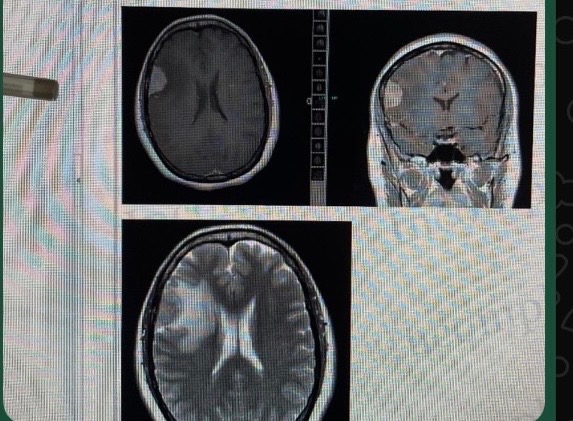

A week ago, I was diagnosed with a tumor, which led to emergency surgery. Although the operation was necessary to save my health, the medical, hospital, and recovery expenses have been overwhelming.

Hace una semana fui diagnosticada con un tumor, lo que me llevó a una cirugía de emergencia. Aunque la operación era necesaria para salvar mi salud, los gastos médicos, hospitalarios y de recuperación han sido abrumadores.